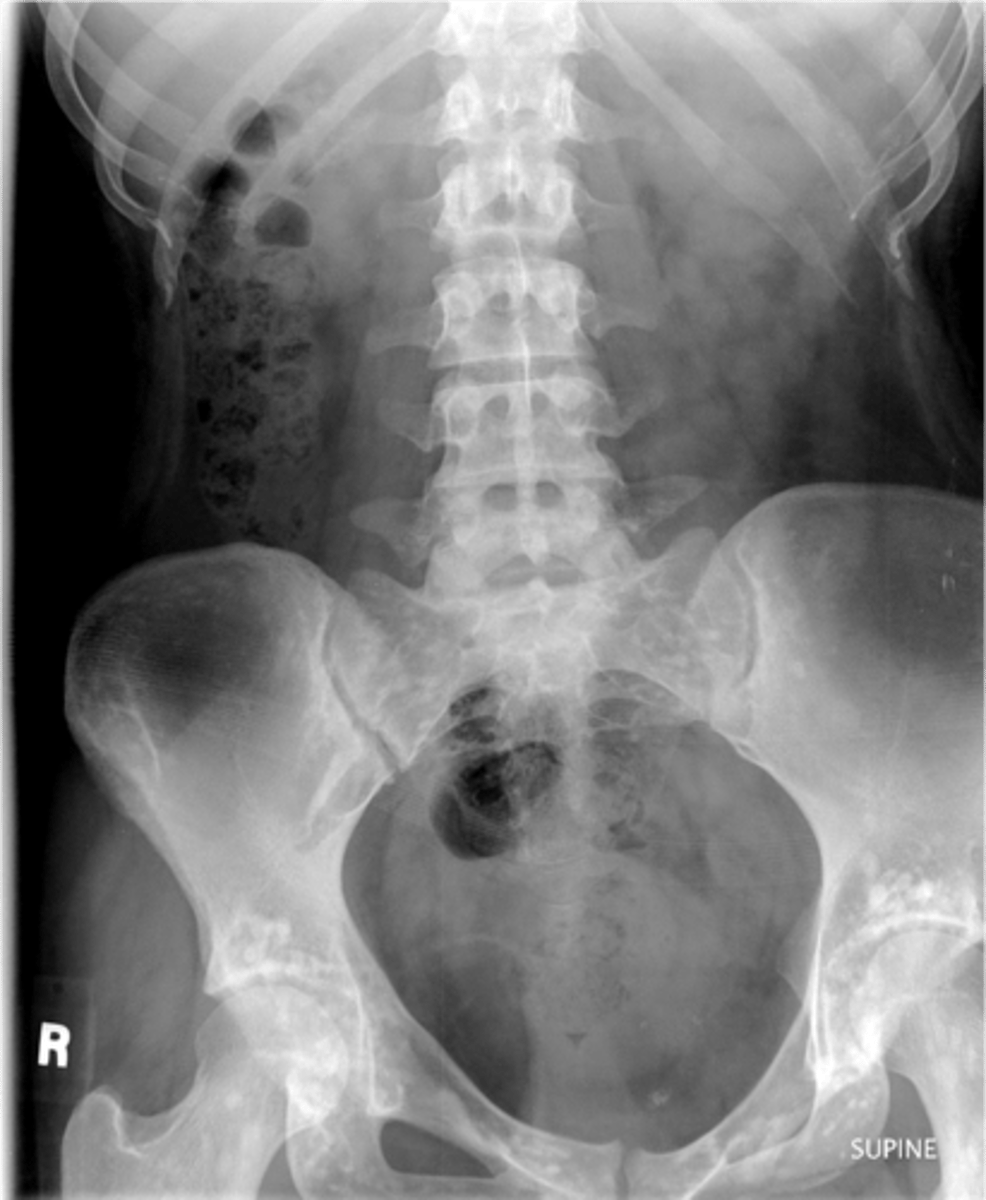

Osteopoikilosis

Diagnosis?

<p>Diagnosis?</p>